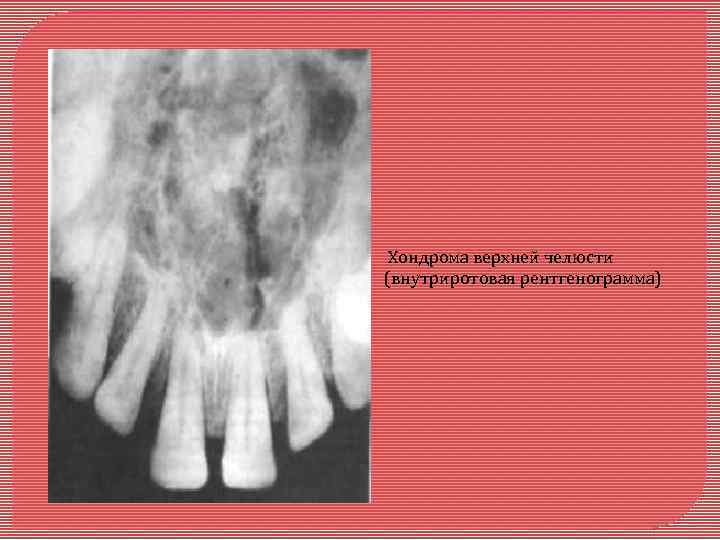

Хондрома - доброкачественная опухоль из хрящевой ткани. Локализация: передний отдел верхней челюсти. Макроскопически: представлена узлом дольчатого хрящеподобного вида. Опухоль может располагаться в глубине челюсти (энхондрально) или под периостом (экхондрально). Микроскопически: зрелый гиалиновый хрящ с беспорядочным расположением хондроцитов без признаков атипизма. Иногда обра зуются очаги миксоматоза и вторичной оссификации с образованием костных балочек.

Хондрома верхней челюсти (внутриротовая рентгенограмма)